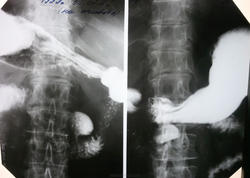

Рентгеноскопия - дивертикул 12 перстной.

Эта круглая тень действительно дивертикул. Вы четко просмотрели пассаж по 12-перстной кишке? Перед указанным дивертикулом есть небольшой участок неравномерного контрастирования просвета, там, где может проходить верхняя брыжеечная артерия. Синдром сдавления не всегда дает ярчайшую клиническую картину, а рентгенпризнаки есть.

Перед указанным дивертикулом есть небольшой участок неравномерного контрастирования просвета, там, где может проходить верхняя брыжеечная артерия. Синдром сдавления не всегда дает ярчайшую клиническую картину, а рентгенпризнаки есть.

Пациентка 1933г. Жалобы на эпизоды давящих болей в эпигастирии. В анамнезе холецистэктомия.

Столкнулась с СВБА совсем недавно. Правда, случай был довольно запущенный с перипроцессом, смотрели в несколько глаз, пациент прооперирован, но продольности не видела. До сужения обычная слизистая, но диаметр кишки до 5,0 см, а далее стойкий дефект и опять более-менее нормальная слизистая. Может быть на начальных стадиях что-то изменяется?